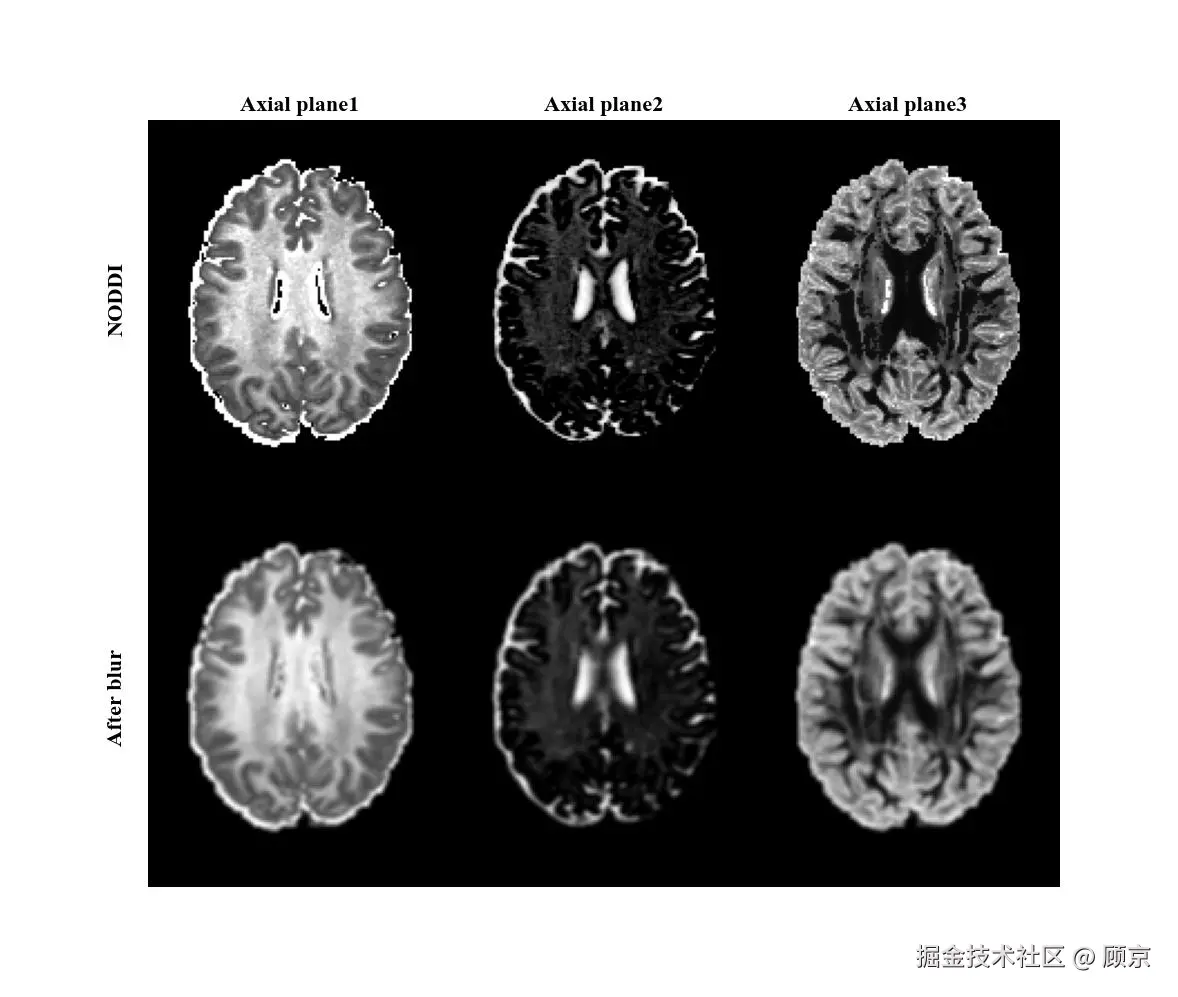

其中,xxyy是像素相对于核中心的偏移,σ\sigma是标准差,可以决定模糊程度。通过这个高斯核对图像进行卷积,就可以实现高斯模糊,如图6所示。

图6 高斯模糊操作